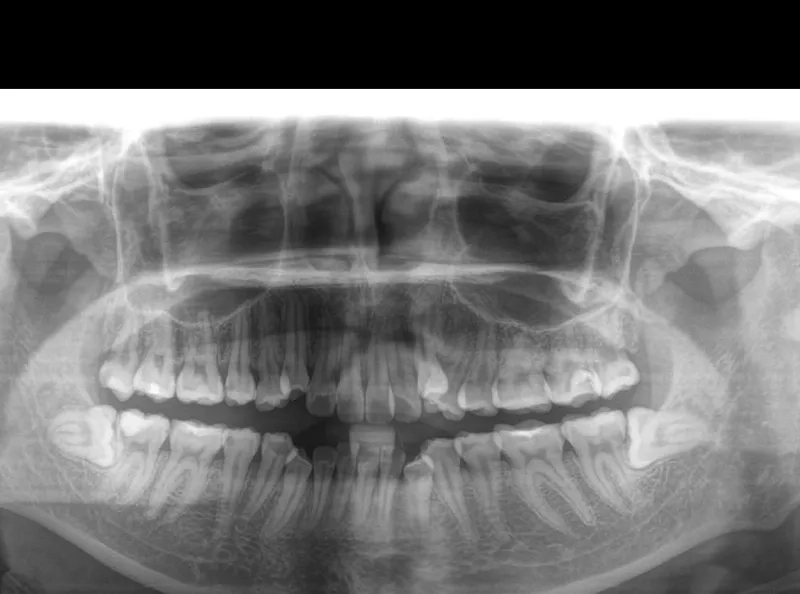

Chính vì là kẻ đến sau cùng, răng khôn thường không tìm được vị trí thuận lợi để mọc thẳng. Chúng phải tìm cách chen chúc, dẫn đến các tình trạng phổ biến như mọc lệch, mọc ngầm dưới nướu hoặc đâm ngang vào chiếc răng số 7 bên cạnh.

Hủy hoại cấu trúc răng số 7 lân cận

Khi răng khôn mọc lệch hoặc đâm ngang, nó sẽ trực tiếp húc vào chân răng số 7. Lực đẩy này diễn ra âm thầm nhưng mạnh mẽ, làm tiêu chân răng, gây sâu răng số 7 và có thể khiến chiếc răng này bị lung lay hoặc mất vĩnh viễn.

Nguy cơ hình thành u nang xương hàm

Trong một số trường hợp răng khôn mọc ngầm hoàn toàn trong xương, các mô bao quanh răng có thể phát triển thành u nang.

Nếu không được phát hiện qua phim chụp X-quang, u nang này sẽ âm thầm phá hủy xương hàm, làm tổn thương các dây thần kinh và các răng xung quanh, gây ra những tổn thương nặng nề khó phục hồi.